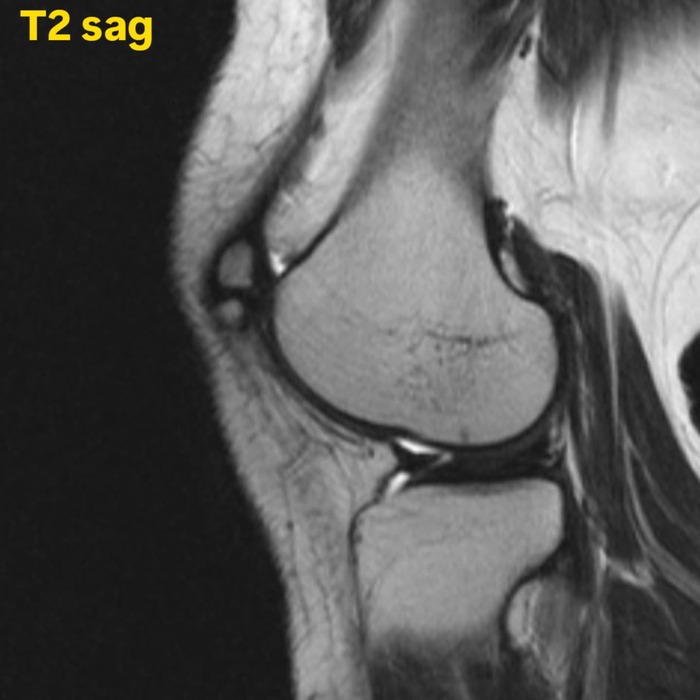

Удвоение надколенника (Bipartite patella) — это коленная чашечка с несросшимся дополнительным центром окостенения, обычно расположенным в верхненаружной части надколенника.

Ровность кортикального слоя костного фрагмента, отсутствие отёка костного мозга и нормальное хрящевое покрытие, помогает исключить травму.

По данным различных источников, удвоение надколенника встречается достаточно часто, и составляет 1% от общего числа обратившихся пациентов. В лучевой диагностике этот процент гораздо ниже, так как patella bipartita чаще всего существует без клинический проявлений.